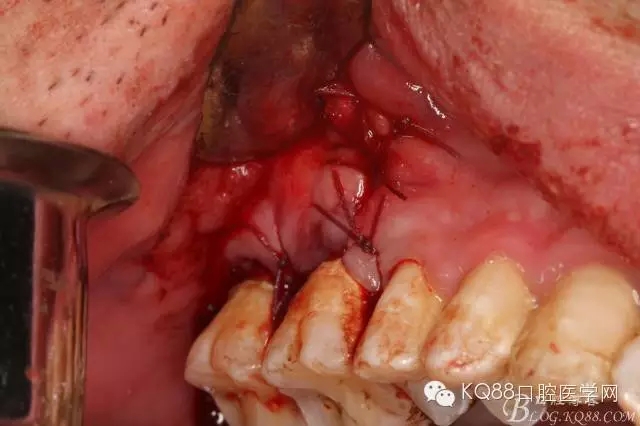

圖10.去除了覆蓋在18牙冠表面的肉芽組織,暴露出18的部分牙冠。

圖11.千辛萬苦,總算看到18的合面了,唯一難做的就是牙齒在里面打轉(zhuǎn)轉(zhuǎn),固定不住牙,也無法夾持住它,好郁悶。

圖12.沒辦法,只能往16旁邊去了點骨質(zhì)。才把18它呼喚出來。病人說他的嘴巴快被拉扯了。

圖13.取出18后,出現(xiàn)的巨大空腔,上頜竇粘膜完全破損。